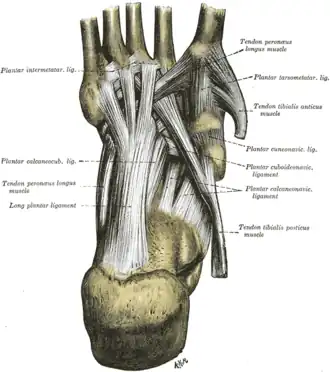

Ligaments of the sole of the foot, with the tendons of the peronæus longus, tibialis posterior and tibialis anterior muscles. | |